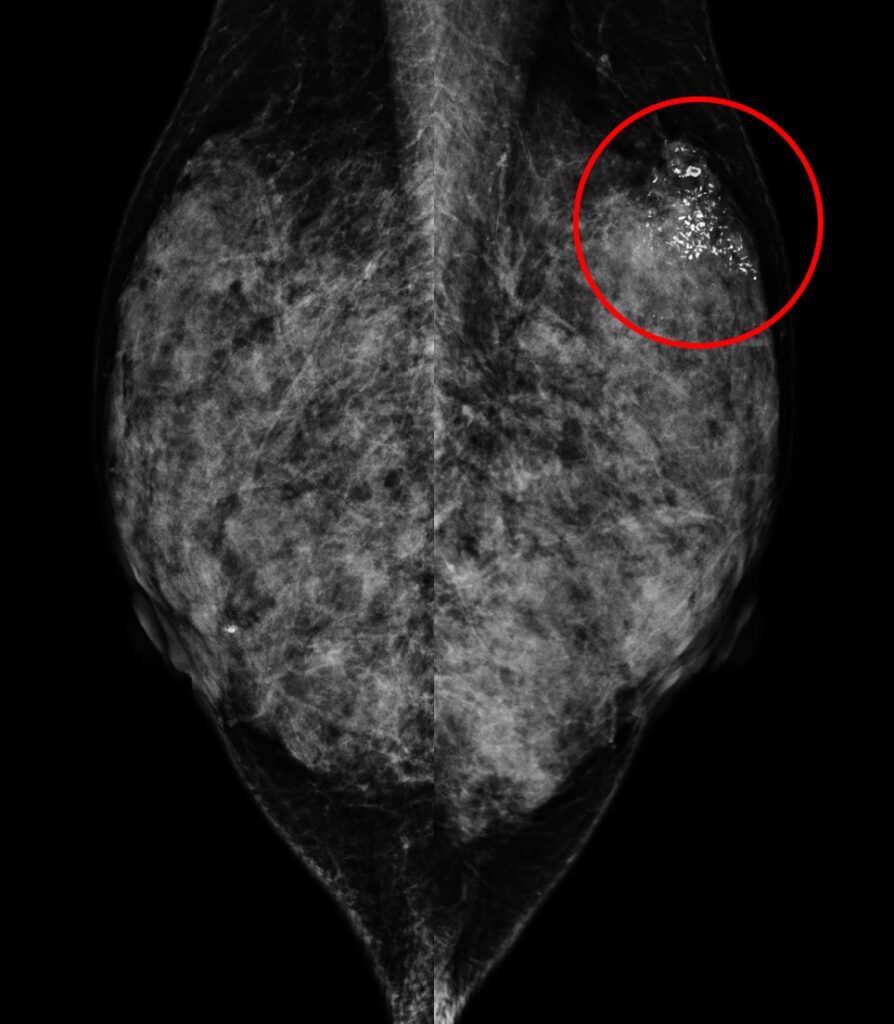

乳房X光攝影

61歲女性於國健署「乳房攝影篩檢」發現:左乳上方有一不尋常的群聚鈣化點、經手術證實為乳房原位癌,後續恢復良好。